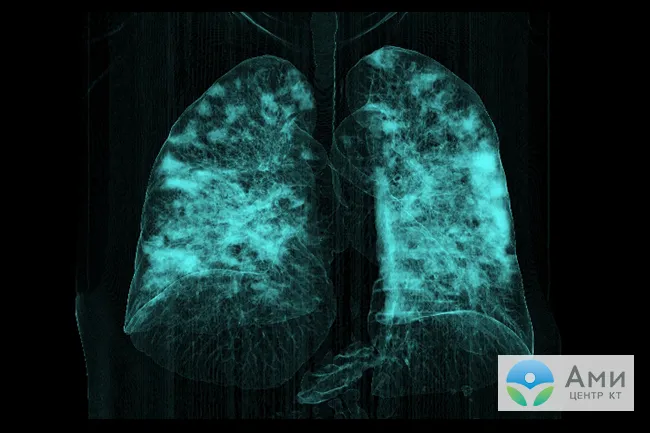

Поражение легких при вирусной пневмонии

Инфильтрация легких при вирусной пневмонии на 3D-реконструкции дыхательных путей (КТ-3)